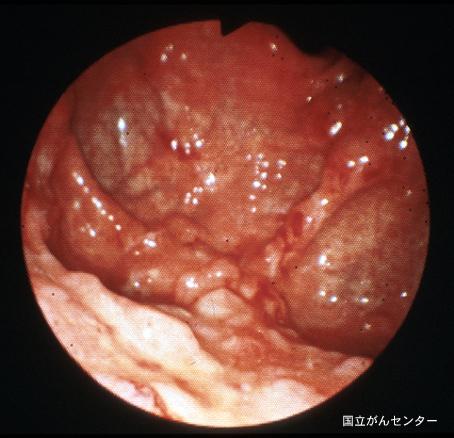

진행위암과 유사한 형태를 보인 위의 악성 림프종

[Image-ID:6251]

악성 림프계종양/악성 림프종

위(부위)/2개 이상

내시경

40이상

ss(a1)